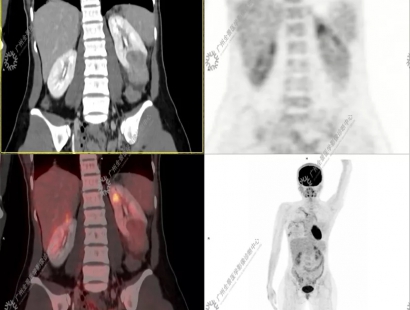

24岁的陈女士(化名)无明显诱因出现右肩背部疼痛、呼吸困难5天,在当地医院检查提示右侧液气胸,右肺压缩近98%,遂留置胸腔闭式引流管,同时肺部CT发现双肺多发“肺大泡”。在住院期间患者常规超声检查偶然发现左肾下极一较大肿块。当地医院CT检查提示为肾癌合并肾门淋巴结转移。为进一步全面评估患者分期,医生建议行petct全身检查。

检查提示陈女士右侧少量气胸,双肺散在薄壁空腔;左肾下极稍高密度肿块,糖代谢轻度增高(SUVmax为3.40);左肾门增大淋巴结,糖代谢未见增高。综合考虑肺淋巴管肌瘤病,左肾下极肿块为乏脂肪型错构瘤可能性大,需鉴别肾癌。

由于左肾肿块较大,陈女士决定手术治疗,最终左肾肿块病理诊断:血管平滑肌脂肪瘤,这一检查结果与petct诊断结果不谋而合。